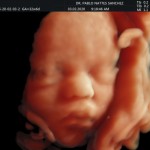

Modalidad de imagen ecográfica que permite evaluar, medir y capturar estructuras fetales superficiales e internas en 3 dimensiones (3D) y también en movimiento y en tiempo real (4D) con programas de realismo aumentado (HD LIVE) e imágenes tomografías fetales (TUI) mejorando significativamente la precisión en las mediciones fetales y la documentaciones de estructuras anatómicas.

Esta tecnología se puede utilizar desde la 6ta a la 40ma semana de embarazo.